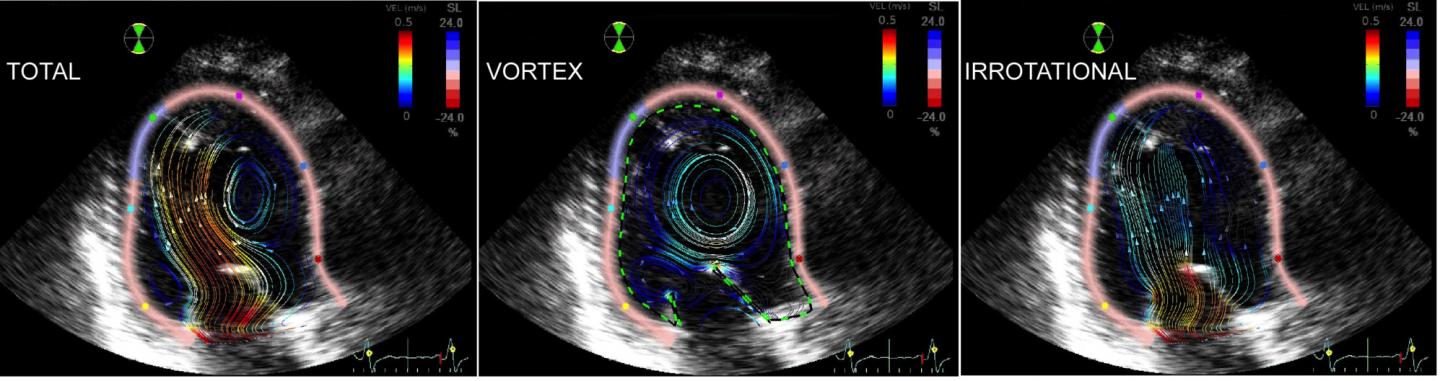

Engineers at the University of California, San Diego have determined for the first time the impact of a ring-shaped vortex on transporting blood flow in normal and abnormal ventricles within the human heart. They worked with cardiologists at the Non-Invasive Cardiology Laboratory at Gregorio Marañon Hospital, in Madrid, Spain.

All subjects underwent comprehensive 2D echocardiographic exams. Then, engineers processed the images with methods typically used to create flow simulations for the aeronautical and naval industries, capturing the blood flow inside each subject's hearts.

Researchers found that the ring-shaped vortex helps to allocate about 15 percent of the blood flow within the left ventricle in healthy patients; roughly 20 percent in patients with non-ischemic dilated cardiomyopathy; but only about 5 percent for patients with hypertrophic cardiomyopathy.